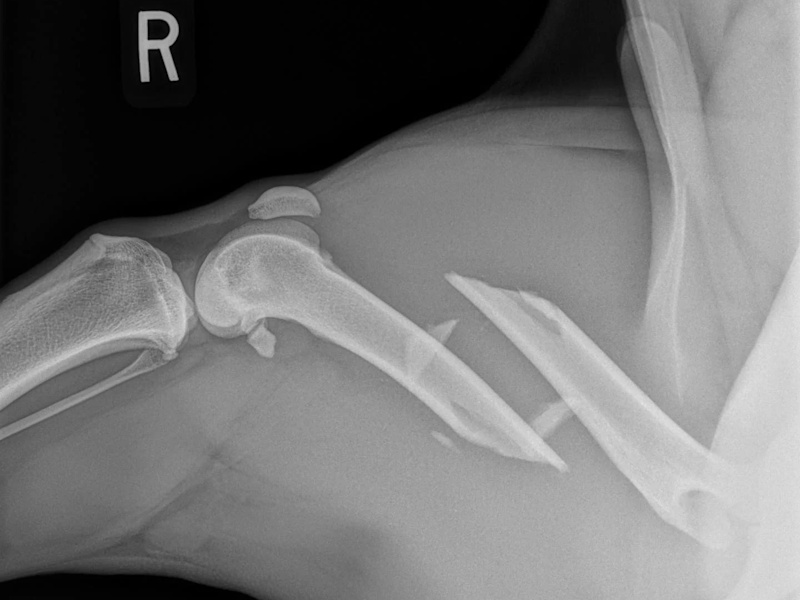

Coxofemoral Luxation (Hip Dislocation)

Hip Dislocation in canines

Treatment Option for Hip Dislocation

Post-op of a Hip Replacement